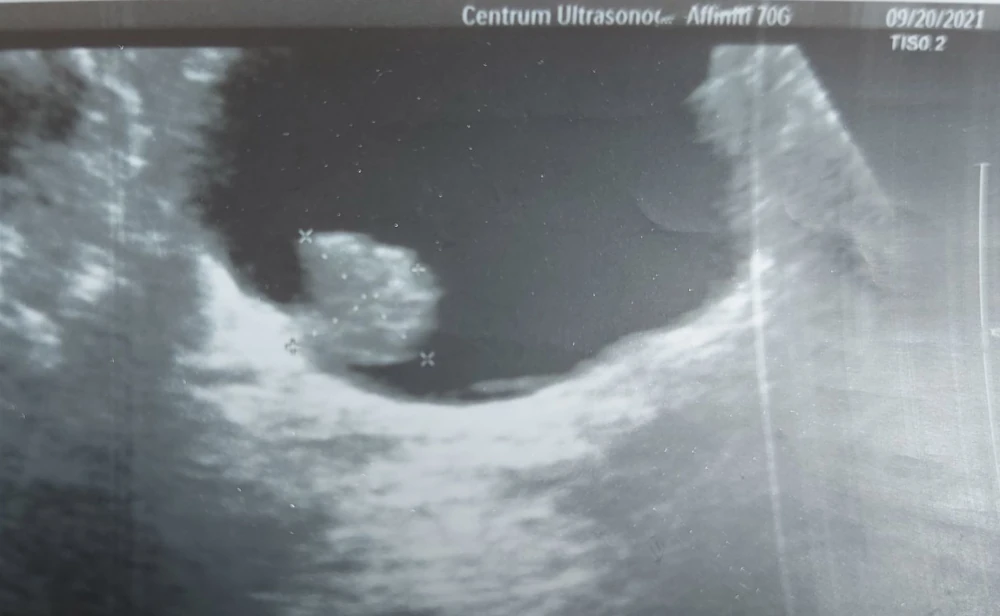

Badanie USG z reguły przeprowadzane jest w pozycji leżącej. Przed badaniem należy odsłonić odpowiednią partię powierzchni ciała. Lekarz smaruje okolicę specjalnym żelem, a następnie przesuwa głowicę aparatu ultrasonograficznego. Obraz ukazuje się na ekranie monitora urządzenia USG, a specjalista wydaje pacjentowi gotowy wynik w postaci opisu oraz zdjęcia.